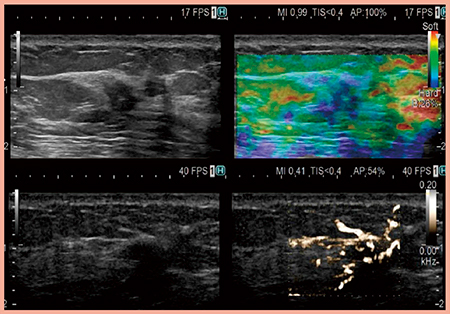

4G CMUTは,周波数が2〜22MHzと超広帯域である上,音響出力が低いため,理論上,ソナゾイド造影超音波が可能である。実際に,乳がんの症例(症例5)を低音圧で撮像したところ,血管の走行がかなり緻密かつ高コントラストに描出された(図5)。乳腺悪性リンパ腫においても同様の画像が得られている。腫瘍内音速が速くフォーカスがずれやすい病変でも血管のフォーカスが比較的安定しているのは,eFocusingとの相乗効果と考えられる。

症例6は乳がんの術前化学療法後で,造影超音波にて残存する腫瘍血管が明瞭である(図6)。将来的には乳がんの化学療法後に切除を行わない時代が来ると考えられており,その場合,治療方針を決定する上で重要な新生血管の評価に,造影超音波は欠かせないツールになると考えている。

図5 症例5:乳がんのソナゾイド造影超音波

図6 症例6:乳がん術前化学療法後の腫瘍血管の残存の評価